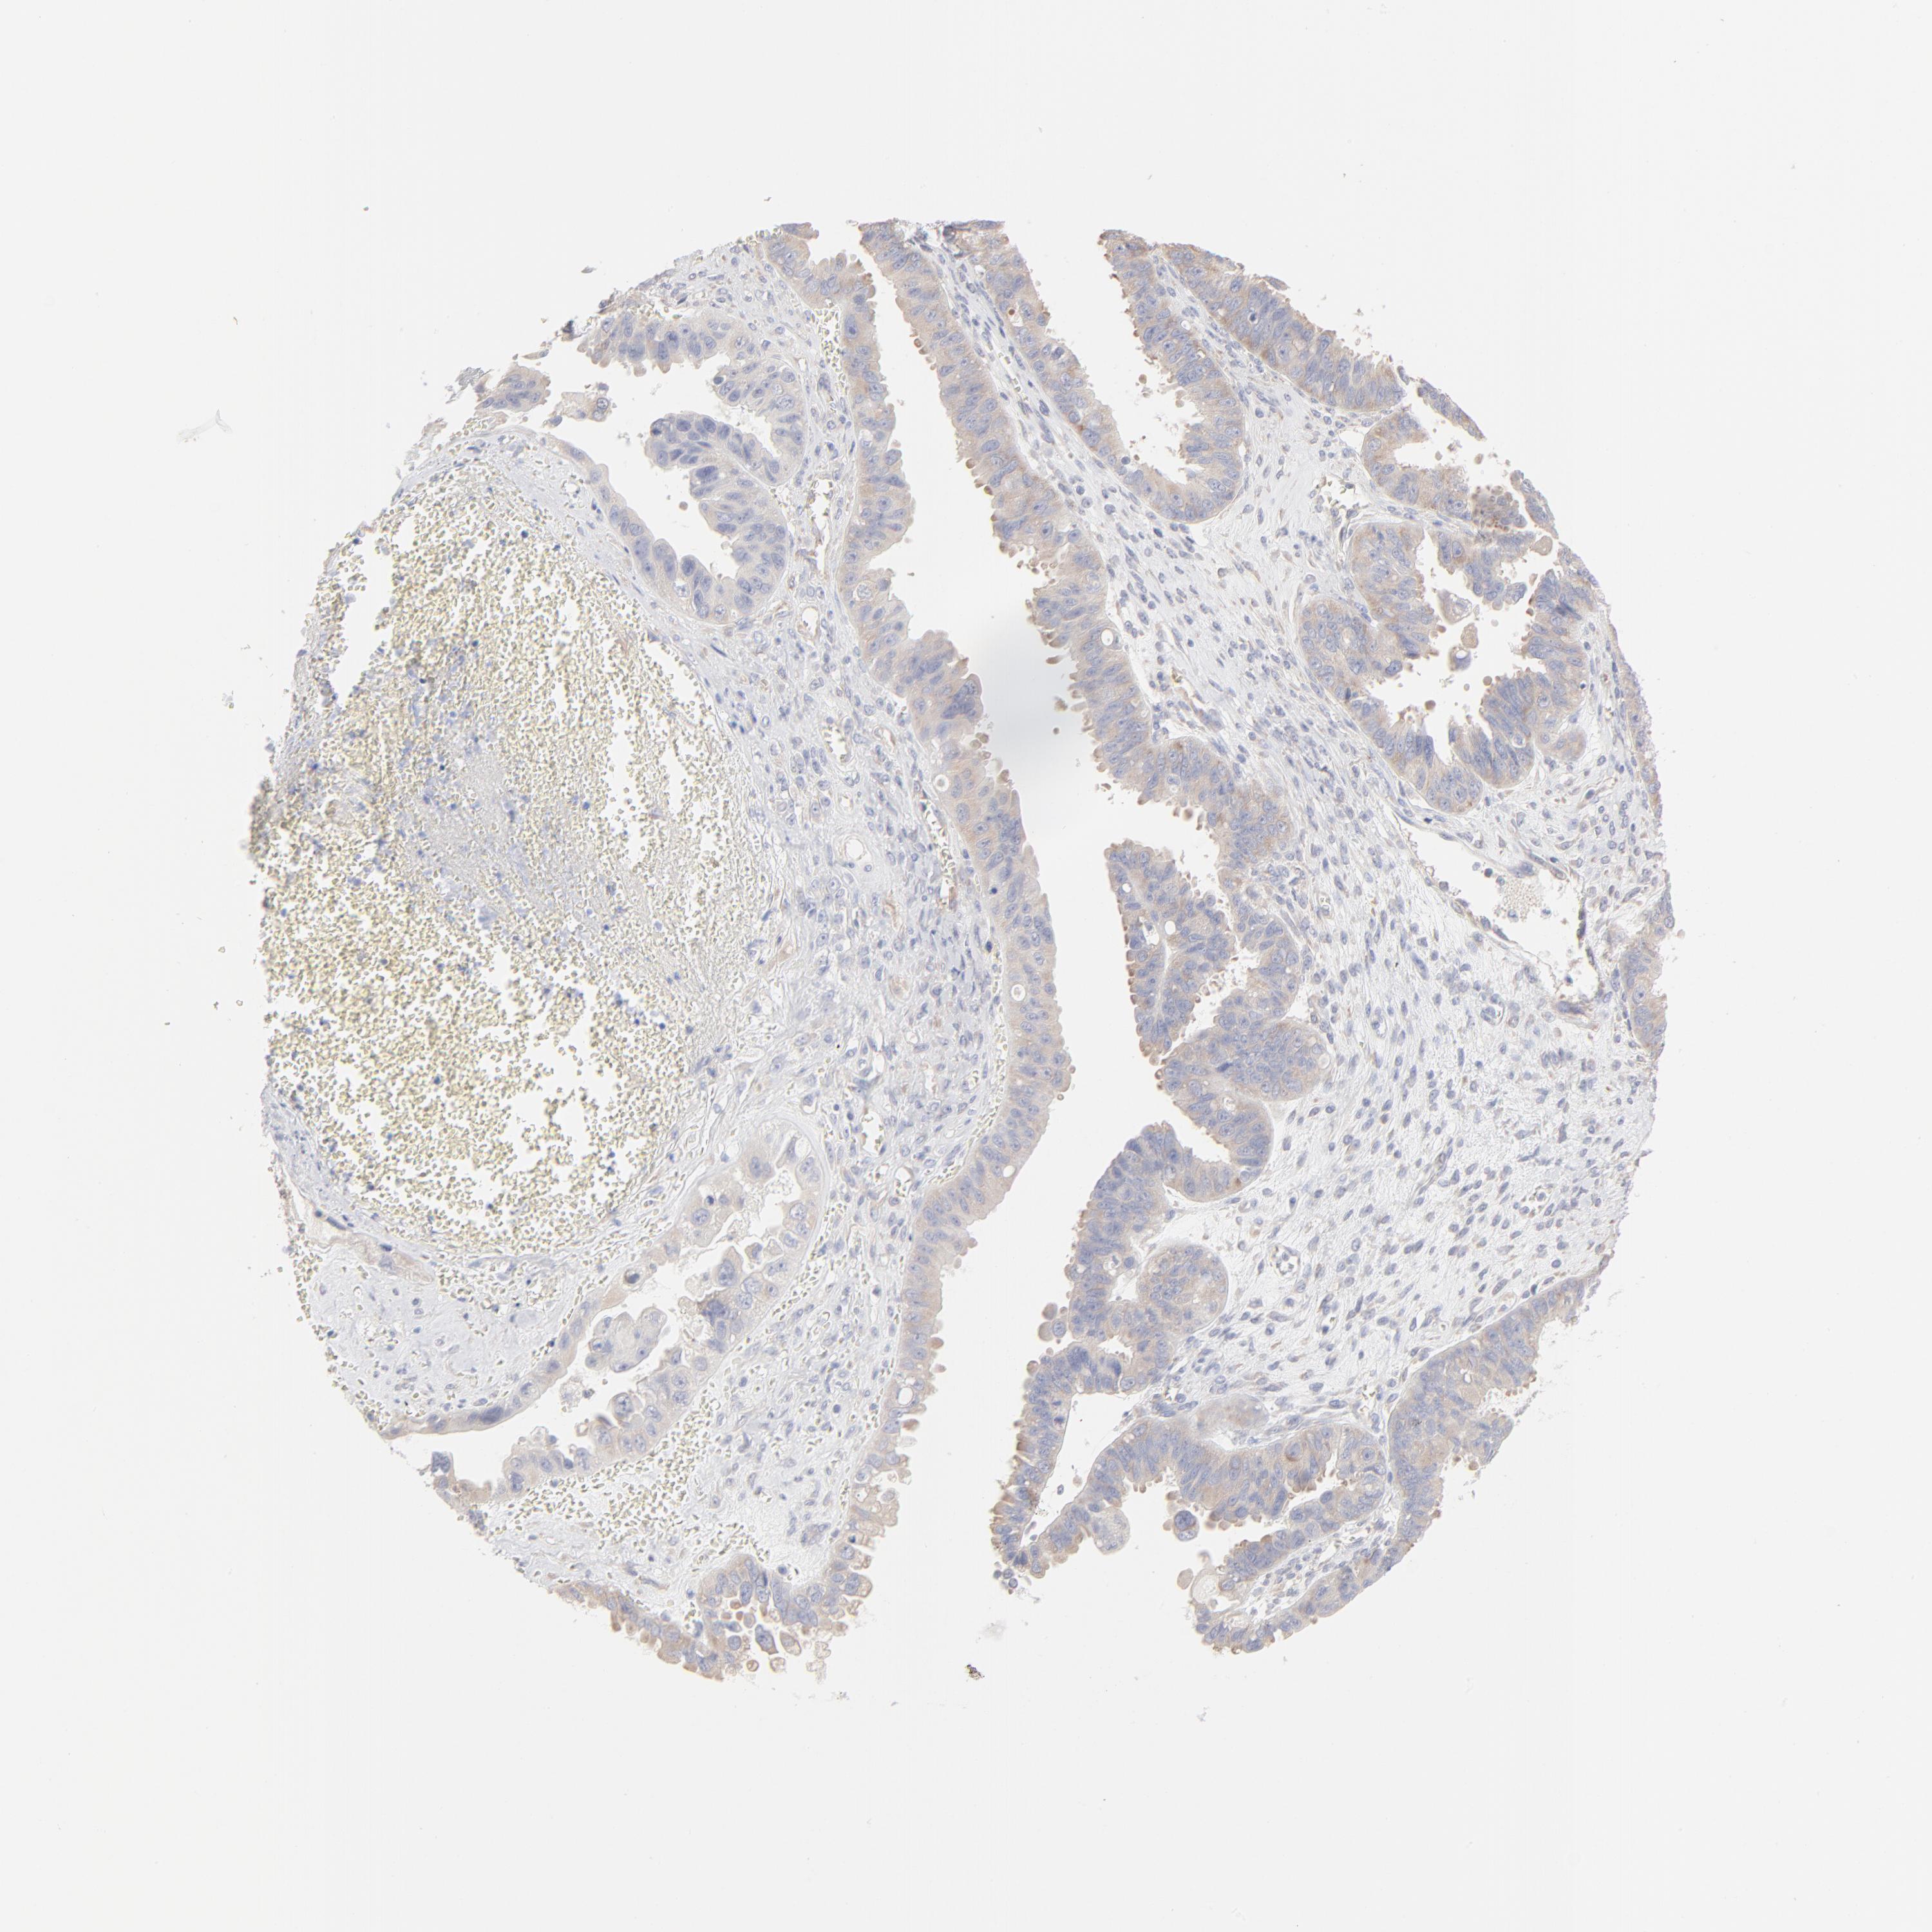

OVARIAN CANCER - Protein expressioni

A mouse-over function shows sample information and annotation data. Click on an image to view it in a full screen mode. Samples can be filtered based on level of antibody staining by selecting one or several of the following categories: high, medium, low and not detected. The assay and annotation is described here.

Note that samples used for immunohistochemistry by the Human Protein Atlas do not correspond to samples in the TCGA dataset.

Antibody stainingi

Antibody staining in the annotated cell types in the current human tissue is reported as not detected, low, medium, or high, based on conventional immunohistochemistry profiling in selected tissues. This score is based on the combination of the staining intensity and fraction of stained cells.

Each image is clickable and will lead to virtual microscopy that enables deeper exploration of all samples and also displays staining intensity scores, fraction scores and subcellular localization as well as patient and tissue information for each sample.

Antibody HPA003371

Staining

High

Medium

Low

Not detected

Intensity

Strong

Moderate

Weak

Negative

Quantity

>75%

75%-25%

<25%

None

Location

Nuclear

Cytoplasmic/membranous

Cytoplasmic/membranous,nuclear

Cystadenocarcinoma, mucinous, NOS

Carcinoma, endometroid

Cystadenocarcinoma, serous, NOS